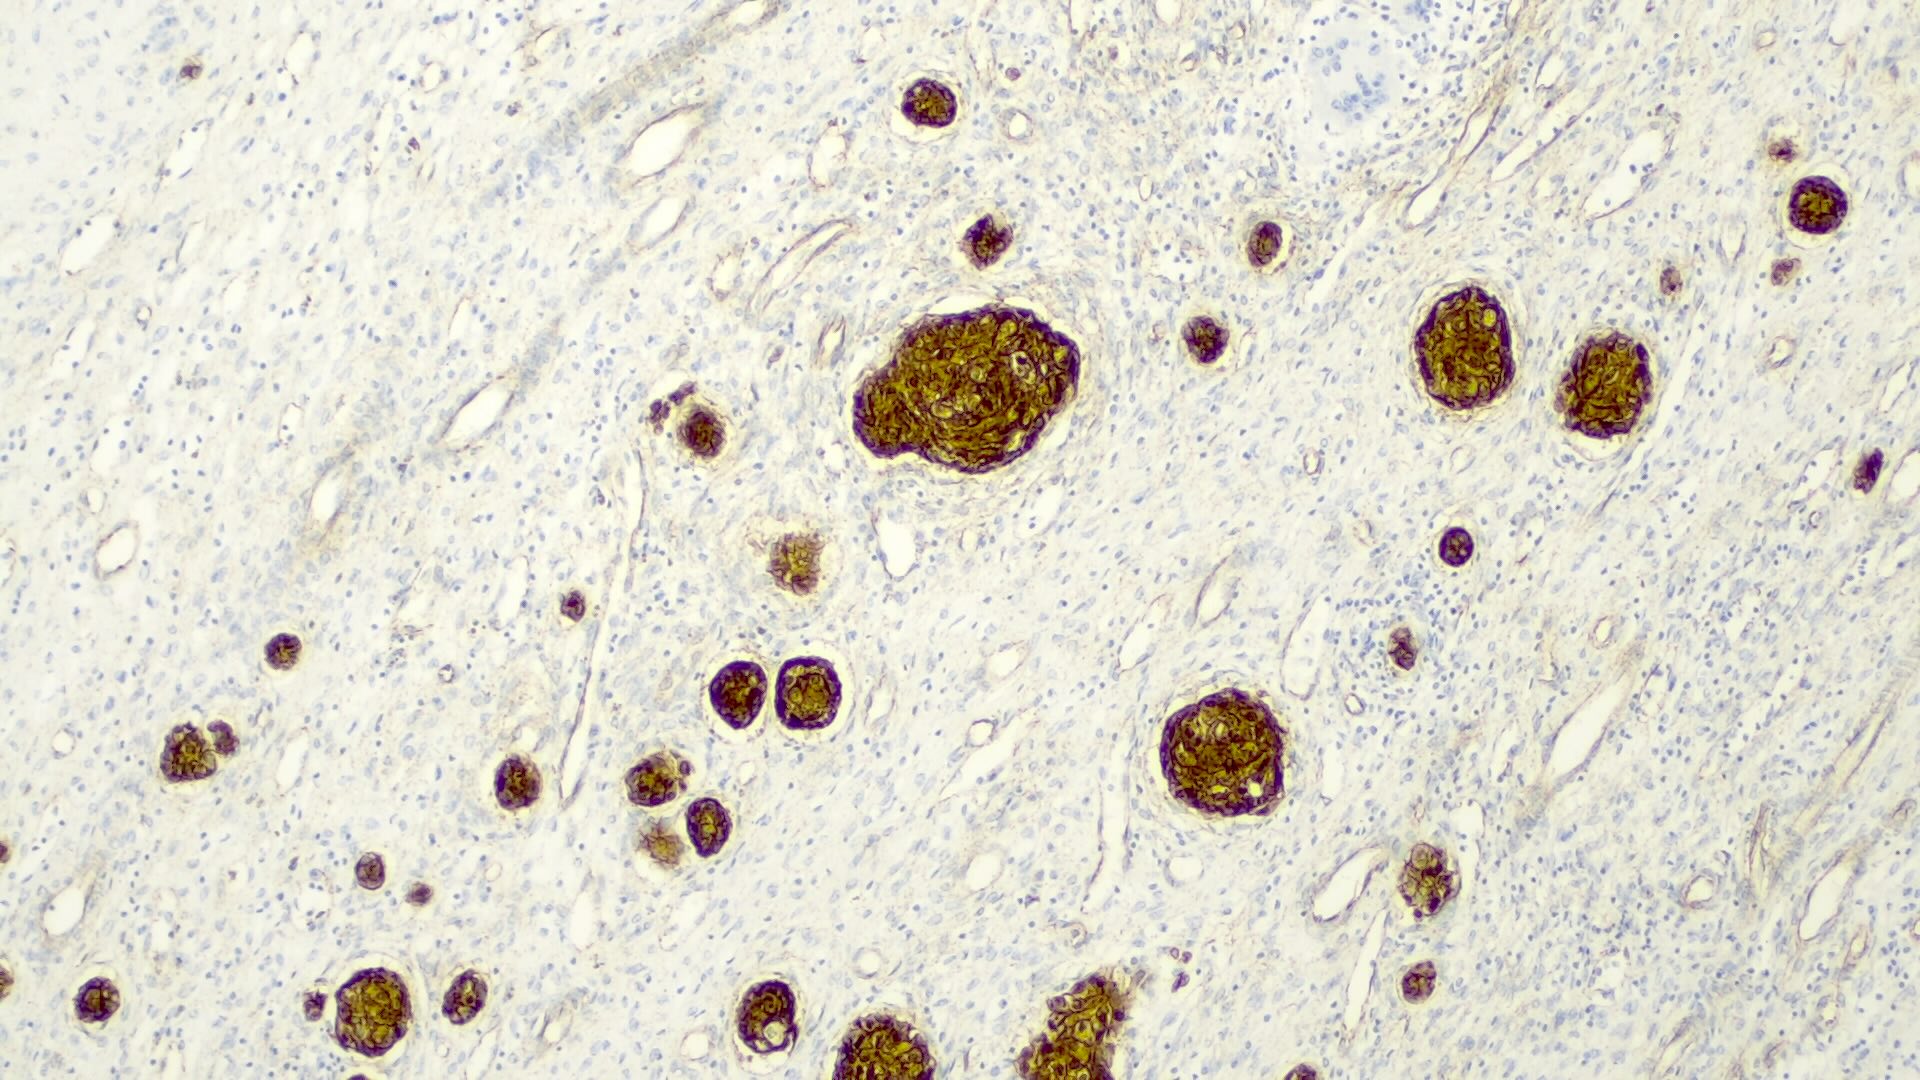

Microscopic (histologic) description

- Classified by the International Pediatric Liver Tumor Consensus Classification as epithelial or mixed epithelial and mesenchymal

- Macrotrabecular pattern

- Thick trabeculae (5 - 12 cells thick)

- Trabeculae may be composed of fetal, embryonal, pleomorphic or hepatocellular carcinoma-like cells

- Mesenchymal pattern (Pediatr Dev Pathol 2020;23:79)

- Mature and immature fibrous tissue

- Osteoid or osteoid-like tissue (more abundant after chemotherapy)

- Hyaline cartilage

Microscopic (histologic) images